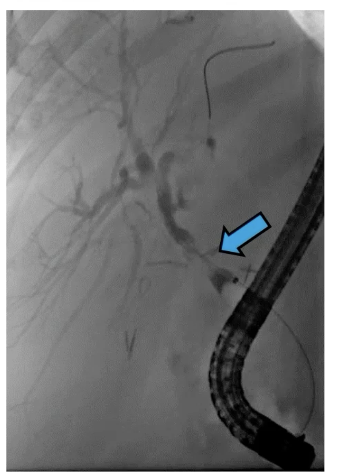

A

Aortoentertic fistula